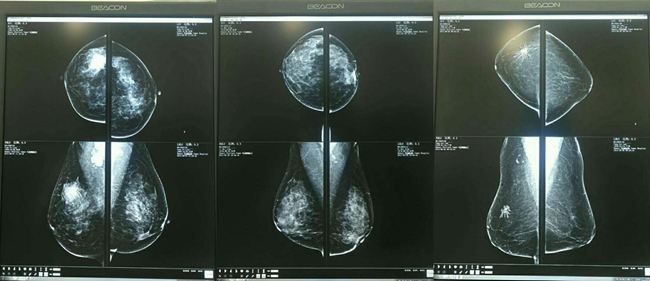

导语:自素股 乳腺病院2017年3月与某人工智能研发科技有限公司联合投入人工智能乳腺钼靶影像诊断研究以来,经过3个多月的训练和实验,该人工智能“乳腺健康检...